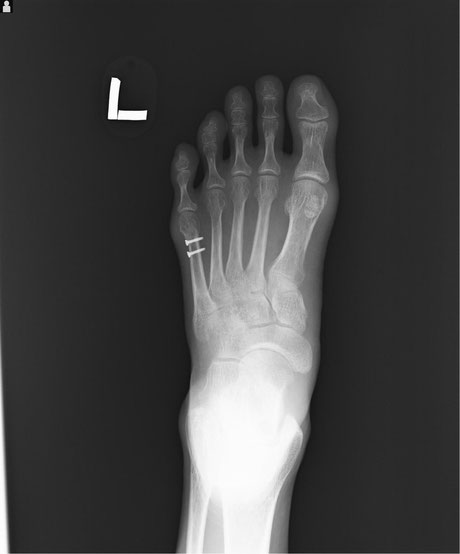

〇第五中足骨骨折

内科で貧血を起こし転倒 安静後立ち上がることができたので帰宅

翌日痛みを訴え来院されました。明らかに骨折の疑いがあるのっで

レントゲン検査を依頼し骨折を確認しました。

病院では通常長靴のようなギプスを巻き、週ごとに骨の状態をレントゲン検査して経過観察していきますが、高齢で足元も不安定なので簡単な副子(あてがう物)と包帯で固定しました。

毎日来院してもらい患部を清潔にし超音波と軽擦(軽くマッサージをして浮腫をとる)をしました。経過良好です。

○第5中足骨骨折

足首をねんざした時に同時に起きる骨折です。

昔から「げた骨折」と呼ばれたもので、当時は下駄のひもが切れた時足の外側が地面に叩き付けられたために骨折したからでしょうか・・?今でも「げた」言えばこの骨折意味します。 整骨院でもよく扱う骨折です。

通常整形外科では足の指先から膝下までのギプスをまき足底にヒールと呼ぶゴムパットをつけます。

ただこのギプスは外も家の中も常にブーツを履いた様なもので、しかもヒールが片方だけにあるので

非常に歩きにくいものです。簡単に言えば片足に10センチのヒールのあるブーツ、片方は裸足といった具合です。

また一ヶ月ほど固定するので夏などは想像したくありません。私も整形外科勤務時はこのギプスを患者さんに巻いていましたが、取り外すときは息を止めてギプスカッターを使用していました。(くさ~)

当院ではブーツの様なギプスは巻かず、副子を外からかぶせ包帯で固定します。

毎日固定は外し患部の清拭、浮腫の除去、動かせる関節は早期からリハビリ。これにより患者さんは気持ちよく過ごすことができます。固定期間からリハビリを開始するので関節の拘縮も防ぎ早期回復につながります。